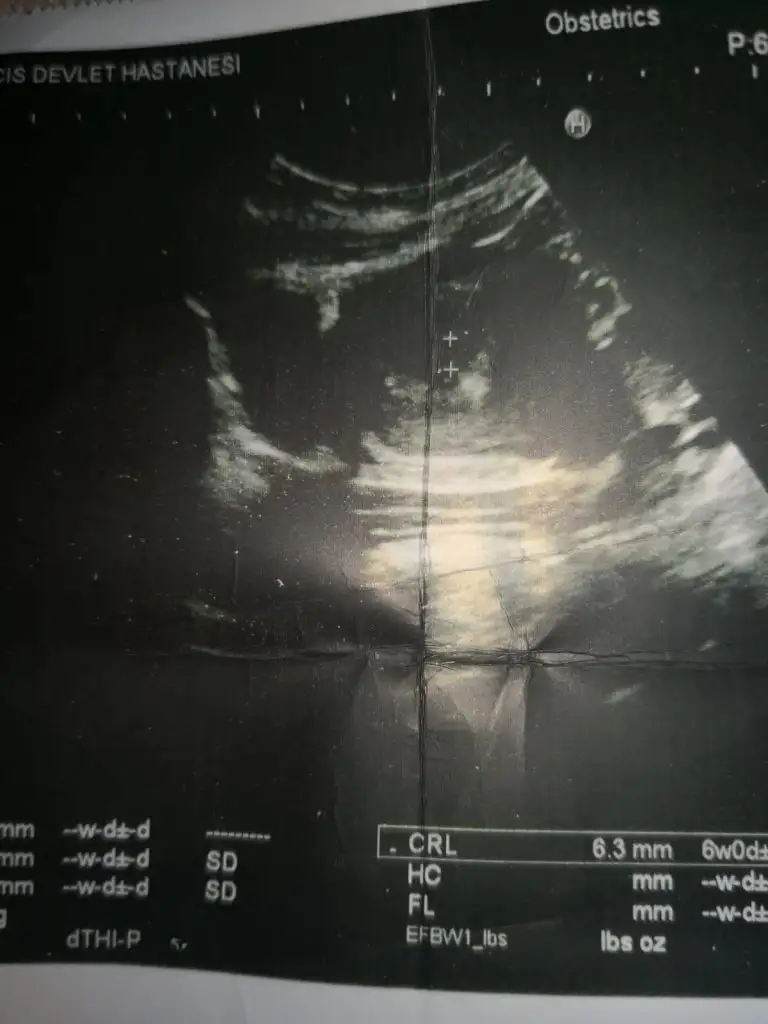

vaginal ultrasonkizlar merhaba. simdi gordum boyle konu oldugunu. benim ilk bebegim, cinsiyeti onemli degil, saglikla ilerleyelim, saglikli dogsun, başka bir şey istemem. ama konuyu gordum, mezeye yazayim dedim. dogru sonuc versede vermesede, tahmin ede bilen varsa eyleniriz birazultrason 6haftalik

Kızlarr ya benimkini de soylermisiniz :) 6 haftalık görüntü karından ultrason